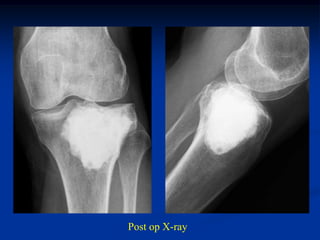

Case #214

25 year male with

adamantinoma tibia

Lateral view

Autoclaved tibia

replaced over IM

nail and rotated 180

degrees